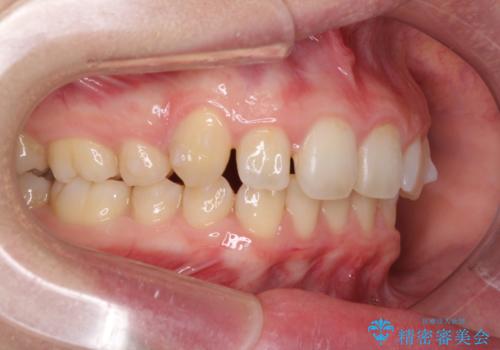

- 八重歯を気にして来院された患者様です。

八重歯の後ろの歯を1歯抜歯し、補助装置(リンガルアーチ)を用いて八重歯の位置を改善し、その後インビザラインにより矯正治療を行うこととしました。

下顎前歯が1本欠損したスリーインサイザーという状態であるため、上下の前歯の咬み込みが深くなったり、奥歯の咬み合わせが理想的なものとならなかったりという仕上がりになってしまいます。

前歯の見た目や奥歯の咬み合わせに、患者様が違和感を感じない状態として治療を終えました。